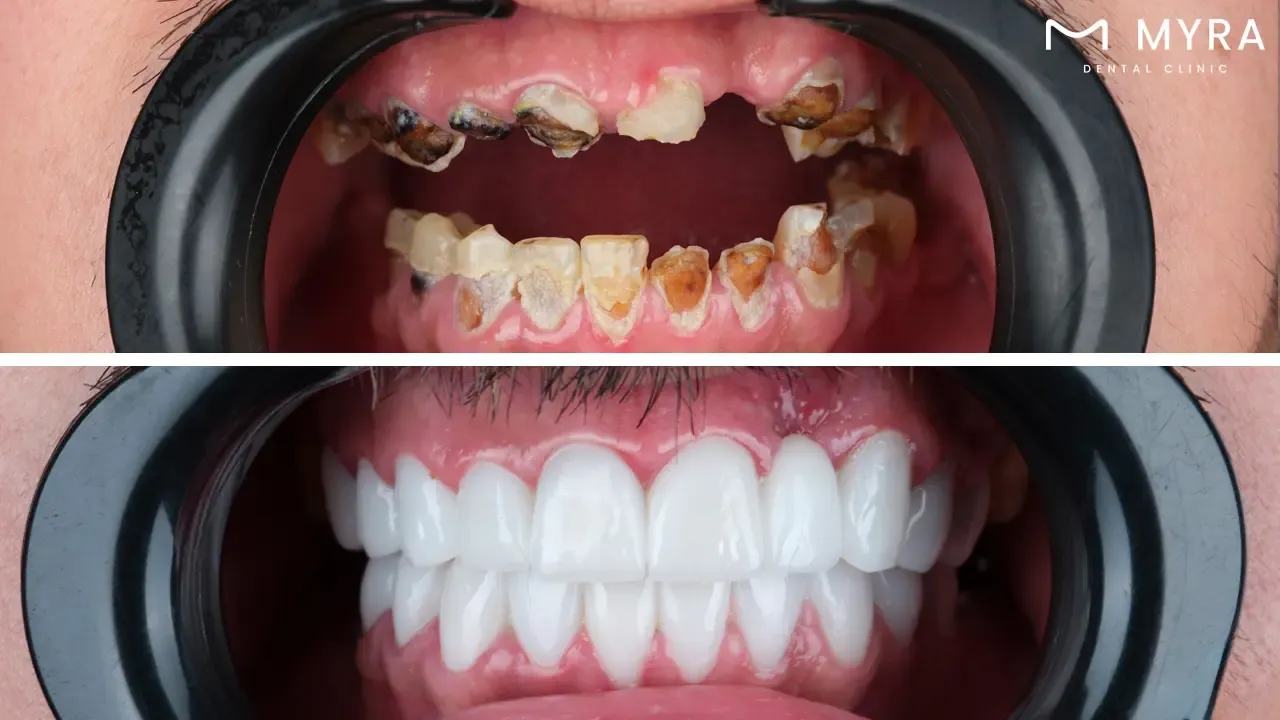

Full mouth rehabilitation, often known as full mouth reconstruction or smile restoration, is a comprehensive therapy technique. Full mouth rehabilitation fully tackles many dental disorders, aiming to restore function and aesthetics to the entire mouth.

Full Mouth Rehabilitation in Turkey: Full mouth rehabilitation, known as full mouth reconstruction or smile restoration, is a complete therapeutic method that aims to restore function and aesthetics to the entire mouth.

Full mouth rehabilitation is a comprehensive and highly individualized dental treatment plan in Turkey. Full mouth rehabilitation is known as full mouth reconstruction or full mouth restoration. Its major goal is to completely restore an individual's oral cavity's function, attractiveness, and overall health. The all-encompassing approach includes a variety of restorative, aesthetic, and even surgical dental operations that are thoroughly performed to address a wide range of dental disorders and concerns.

A full mouth rehabilitation with four dental implants and a full bridge of 12 teeth usually costs around £18,060 in UK. The total price includes the dental implant costs of £7,800 and the full bridge restoration costs of £10,260. However, the same treatment, known as All-on-4 in Turkey, is approximately 60% more affordable in Turkey, offering significant savings without compromising quality. Individuals must contact their dentist to analyze their specific dental requirements and goals to receive an accurate and individualized cost breakdown.

Full mouth rehabilitation with dental implants and a full bridge provides several important benefits. Full mouth rehabilitation offers a holistic solution for people who have dental disorders, addressing functional and aesthetic concerns in a single treatment plan. The use of dental implants provides a sturdy and stable basis for the complete bridge, improving chewing and speaking skills. The entire bridge of 12 teeth provides a natural-looking smile makeover, which results in increased self-confidence and a better overall quality of life. Patients enjoy the benefits of dental implants and well-crafted bridges for many years with proper care, making it a beneficial long-term investment in their oral health and well-being.

There are downsides to consider while whole mouth rehabilitation with dental implants and a full bridge has many advantages. Financial commitment is a barrier for other people in UK and USA. The treatment time is rather long, spanning several months to get the desired results. The surgical part of dental implant insertion requires planning, and there are patients who have temporary discomfort or healing time. The permanent nature of some operations, such as tooth extraction for implants, needs careful preparation and consultation with the dentist before proceeding.

The extensive process takes several weeks to up to six months or more. Full mouth rehabilitation requires numerous appointments, each dedicated to a specific treatment, rigorous planning, and the healing and integration period required for dental implants. The lengthy timeline is due to the requirement for optimal healing, the procedure's step-by-step structure, and the tailored character of whole-mouth rehabilitation. Patients must talk with their dentist in Turkey to determine a realistic timescale adapted to their unique case and treatment plan while keeping in mind that getting the desired outcomes takes several months.